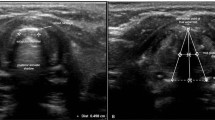

In the ultrasound group, a high-frequency hockey stick probe (L15-7io; Phillips, Andover, MA, USA) was placed along the midline of the neck and the transverse diameter of the subglottic area was measured using ultrasonography (Affiniti70; Phillips), with slight extension of the neck before intubation. Facemask ventilation was stopped to limit fluctuation during ultrasound acquisition. The subglottic transverse diameter was measured using the dimension of the air-mucosa interface within the bilateral inner margin of the cricoid cartilage, which appeared as a round hypoechoic structure (Fig. 1). The narrowest subglottic diameter revealed by the three ultrasound images was selected. Subsequently, the make of the tracheal tube, whose OD was smaller than the selected subglottic diameter, was deemed to be the appropriate size. The difference between the two values was less than 0.5 mm to allow free passage of the tube and adequate sealing. Intubation was performed with this size. The insertion depth was determined by auscultation and confirmed with lung ultrasonography. Lung ultrasonography was performed by placing the transducer on the third intercostal space along the midclavicular line on both sides of the chest for visualizing pleural sliding and lung expansion, which was synchronized with manual ventilation (Fig. 2). The tube tip was advanced gently into the right or left mainstem bronchus, until unilateral lung sound was lost, and pleural sliding and lung expansion was not visualized on one side of the lung on scanning. After confirming the endobronchial position of the tube tip, the tube was withdrawn slowly until bilateral lung sounds were auscultated and bilateral pleural sliding and lung expansion were visible, and then further withdrawn, so that the tube tip was positioned 2 cm above the carina The tube was secured to the lower lip and inflation of tube cuff was determined with the same methods as those used in the conventional group.

Pleural sliding and lung expansion at the lung-chest wall interface in the intercostal lung ultrasonography image. The pleurae appear as hyperechoic linear structures. Backward and forward horizontal sliding movement of the pleurae is indicated for visceral pleural movement against the parietal pleura, which is synchronized with manual ventilation. Two isolated B-lines arising from the juxta-pleural consolidation are projected vertically and thought to result from anesthesia-induced atelectasis. Statistical analyses were conducted using the SPSS software version 25.0 (IBM Inc., Armonk, NY, USA) (https://www.ibm.com/products/spss-statistics).